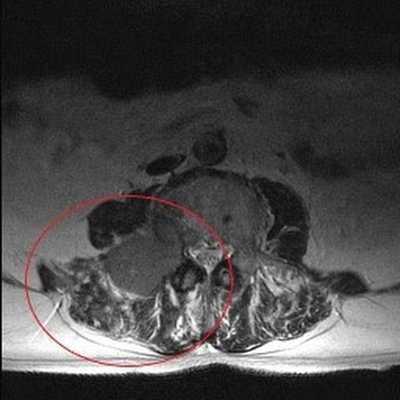

МРТ пояснично-крестцового отдела назначают в тех случаях, когда другие виды исследования не дают четкой картины. Дифференциальная диагностика некоторых заболеваний позвоночника требует детальной визуализации его морфологических элементов и мягкотканных структур. Контрастная МРТ поясничного отдела делается как для уточнения состояния кровеносной системы, так и с целью определения размера и локализации новообразований и воспалительных процессов.

Опухолевое образование (обведено красной линией) на снимке МРТ поясничного отдела в аксиальной проекции